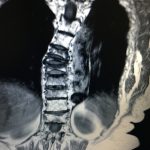

Τα Οστεοπορωτικά Κατάγματα της Σπονδυλικής Στήλης, που είναι και το κύριο αντικείμενο αυτής της μελέτης, έχουν σαν αποτέλεσμα την Κυφωτική και Σκολιωτική παραμόρφωση της (εικόνα 1 α,β) . Οι μεταβολές αυτές συνοδεύονται όπως εύκολα γίνεται αντιληπτό με έντονο πόνο σε όλη την έκταση της Σπονδυλικής Στήλης.

Εικόνα 1 α,β : Μαγνητική Τομογραφία της Σπονδυλικής Στήλης, προσθιοπισθία (coronal) και οβελιαία (sagittal) λήψη, Ακολουθία Τ2. Παρατηρείται η ύπαρξη πολλών οστεοπορωτικής αιτιολογίας καταγμάτων, συνεπεία των οποίων έχει προκληθεί σκολιωτική και κυφωτική παραμόρφωση της Σπονδυλικής Στήλης.